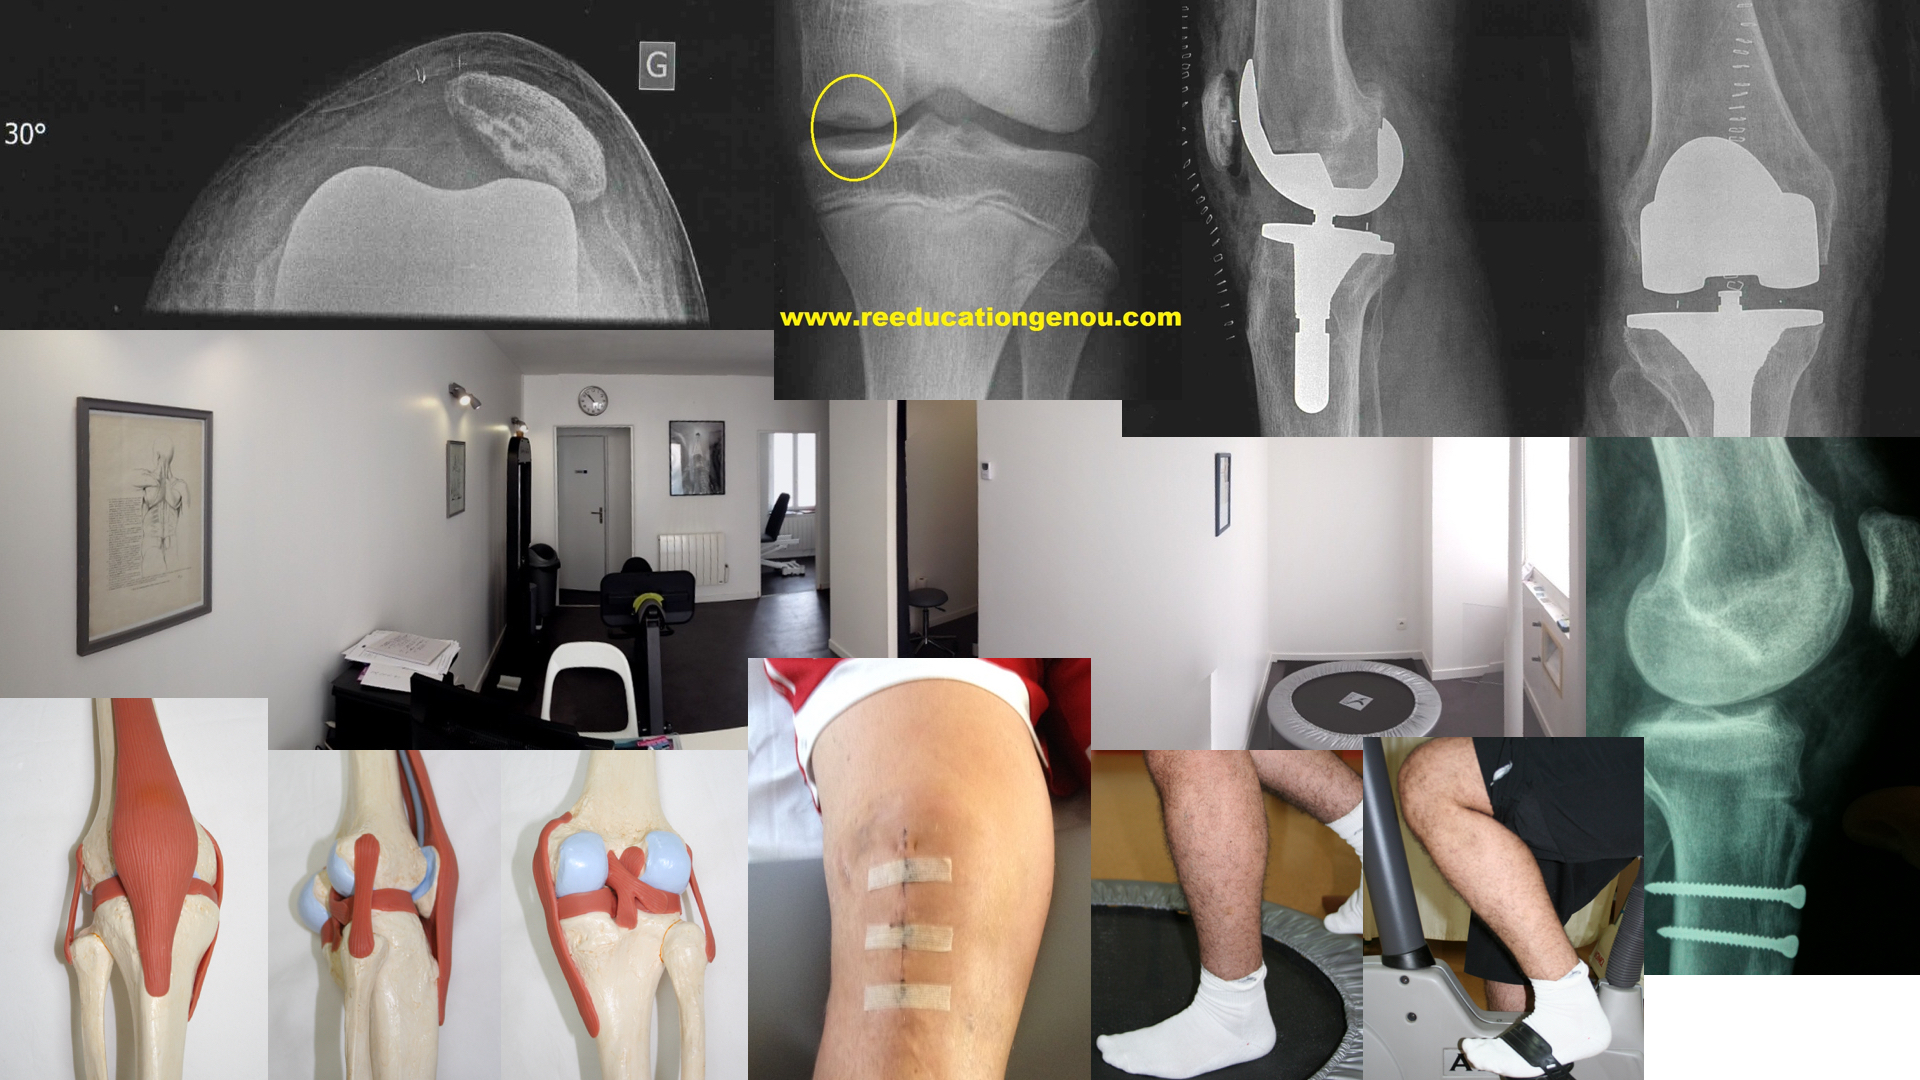

Fracture de la rotule / prothèse fémoro patellaire

LA FRACTURE DE ROTULE

LA ROTULE PROTHETIQUE

Il s'agit en fait de la prothèse fémoro patellaire qui remplace le cartilage consommé de la rotule (par une partie en polyéthylène) mais aussi la partie "en face" sur le femur (par une partie en métal)